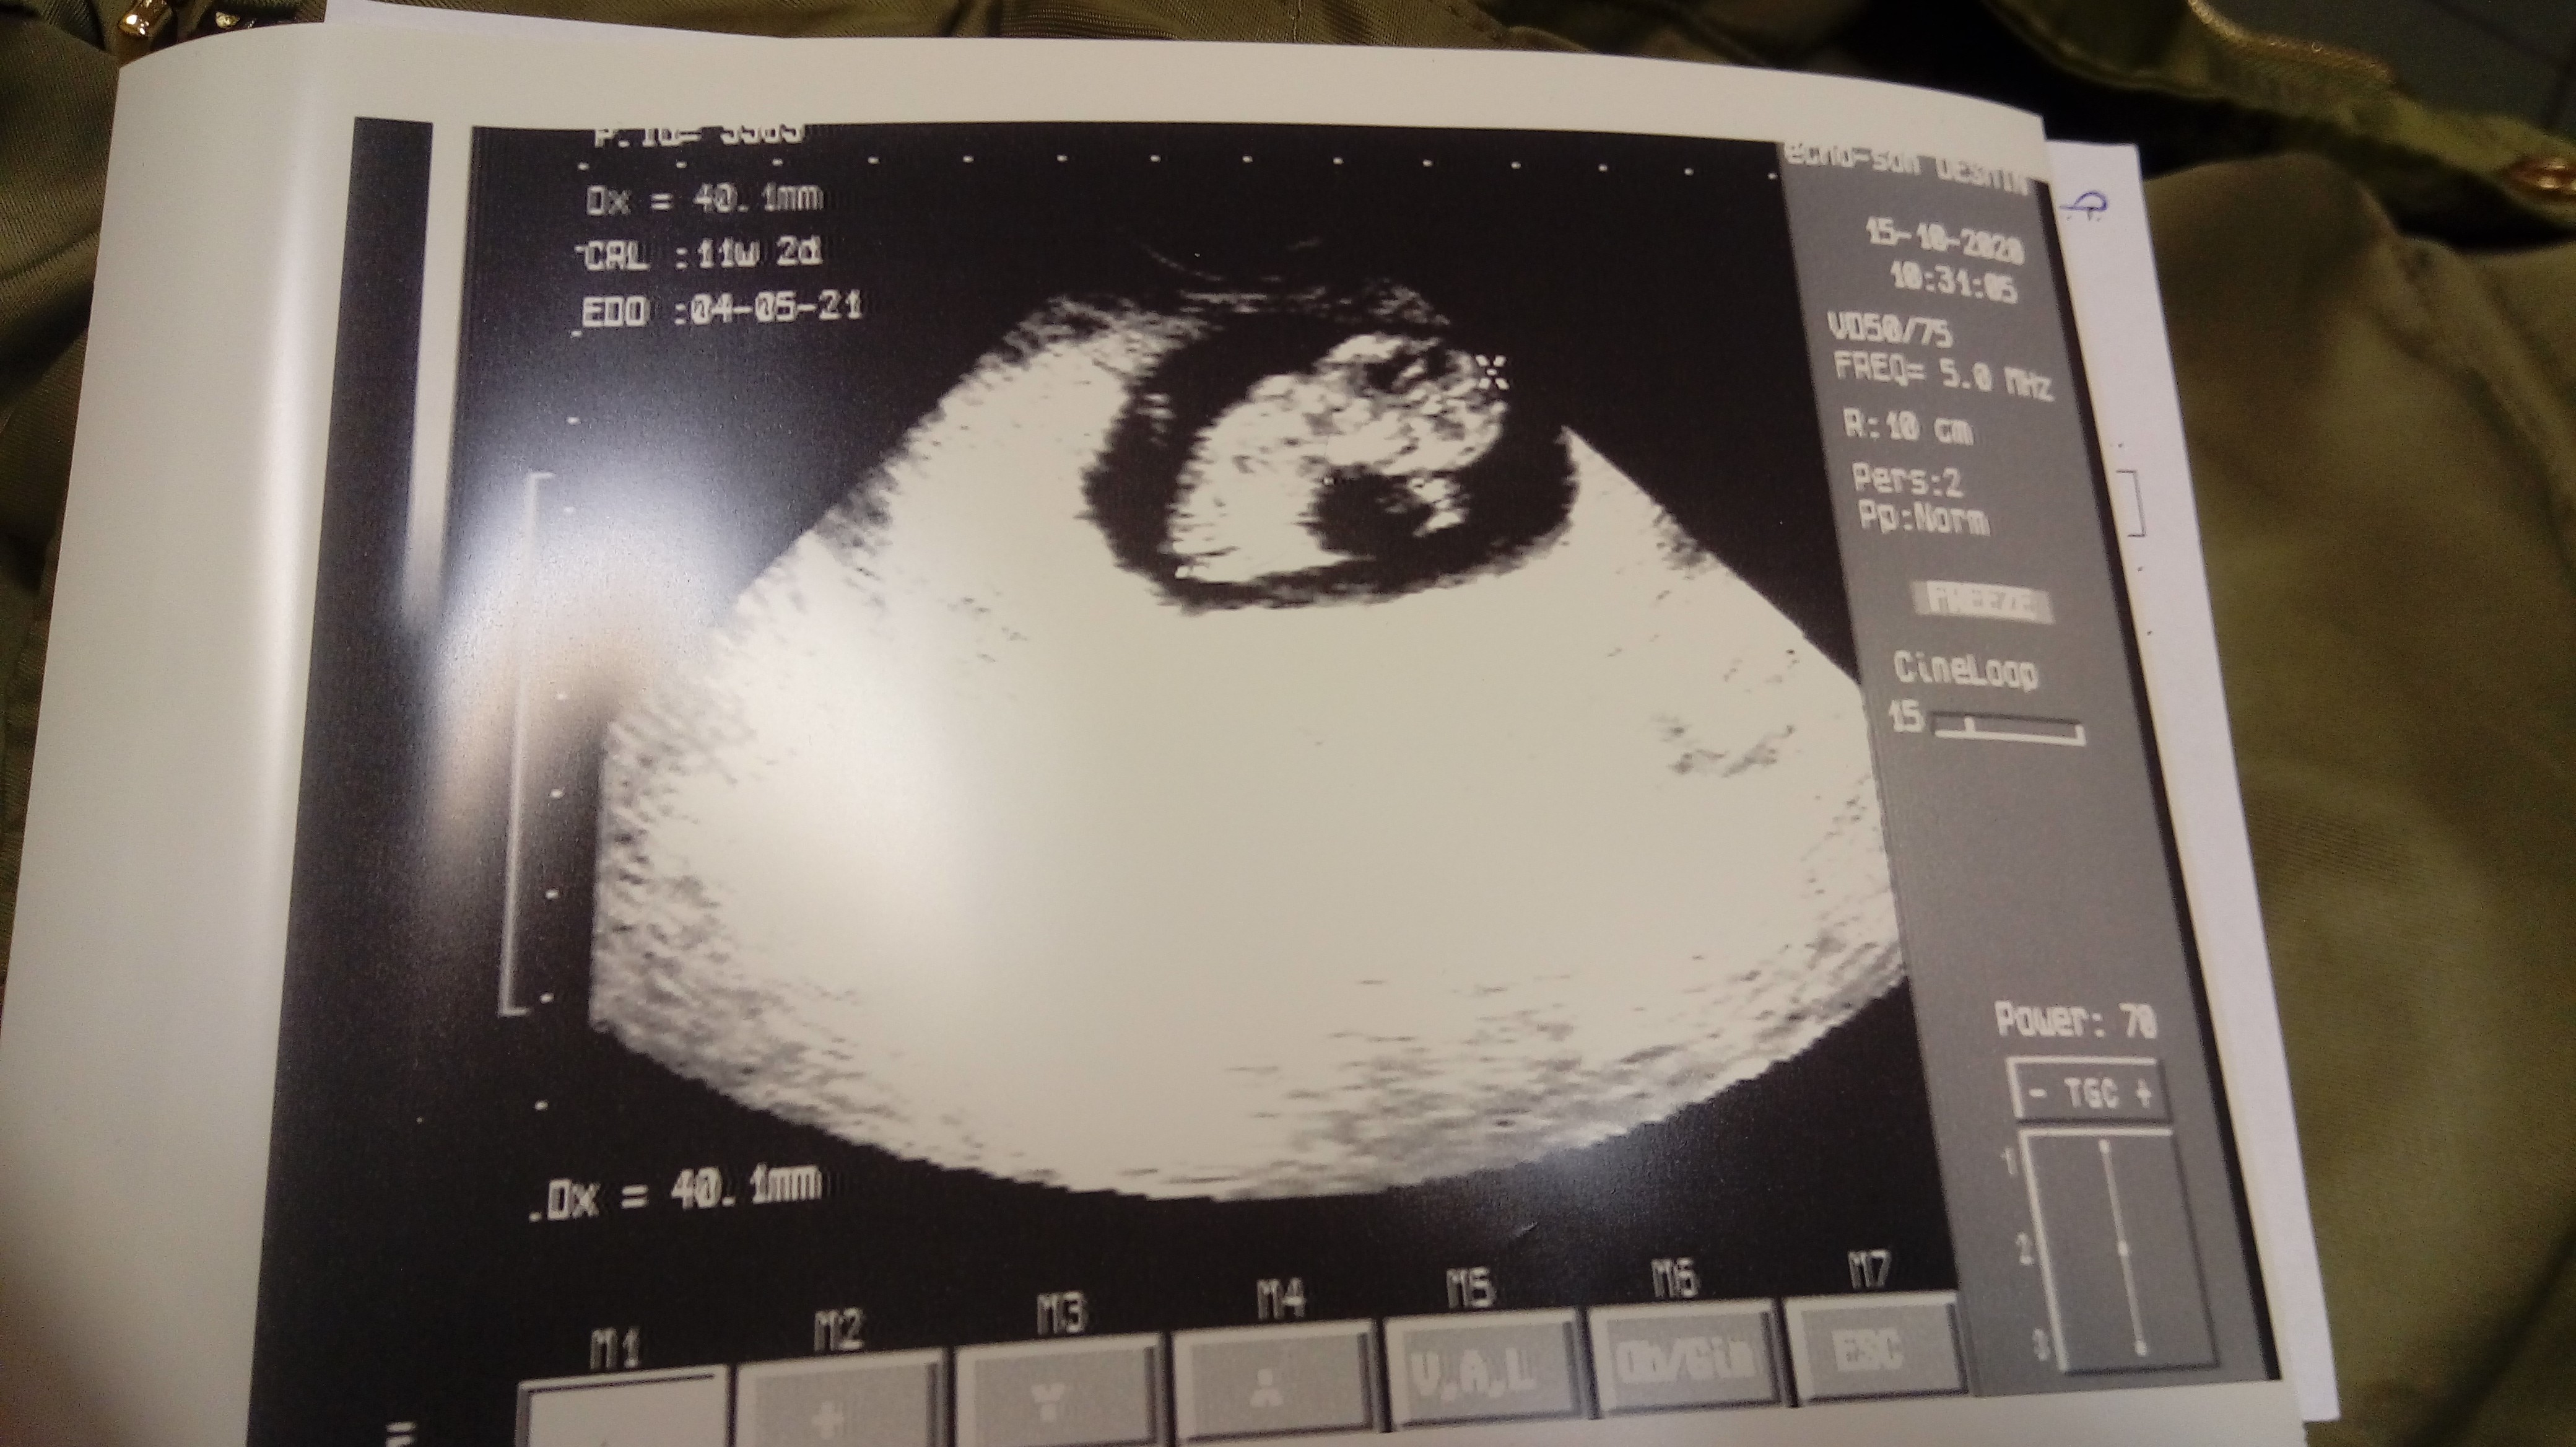

Dziewczynki! U mnie radość. Młode żyje i ma się dobrze 😀 wg crl 11+2. Termin mi sie przesunął z 7 na 4 maja. W takim tempie kwietniowka zostanę. 😂

Załączniki

• 20201015_104840.jpg

20201015_104840.jpg

1,4 MB · Wyświetleń: 93